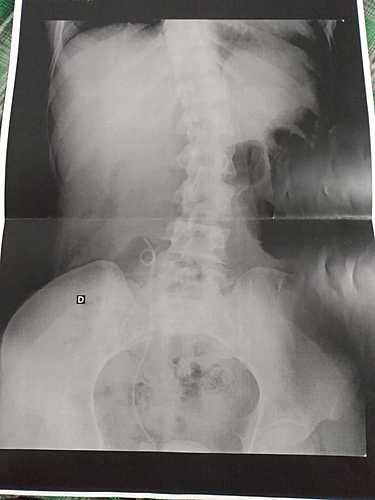

Nesta cirurgia, foi implantado um Catéter Duplo J para melhor funcionamento do meu rim direito. O catéter seria retirado 3 meses depois. Fiz todos os exames pré-operatórios e quando consegui o encaminhamento para marcar a cirurgia com o especialista, surgiu a pandemia.

Então foi adiada, perdi todos os exames, fui internada várias vezes por sentir muita dor, e desde então estou com o Catéter, sinto bastante dor, estou desempregada, tenho 2 filhos, estou vivendo somente da ajuda de minha mãe e de alguns amigos que me ajudam como podem.

Consegui agora novamente a consulta com o especialista, o mesmo passou remédios pra tentar amolecer o catéter pra fazer a retirada. Corro o risco de perder o rim se não conseguir retirar.

Por sentir muita dor e correr o risco de hemorragia, obstrução urinária e infecção pela calcificação do catéter, estou fazendo essa vaquinha pra tentar fazer a cirurgia no particular.